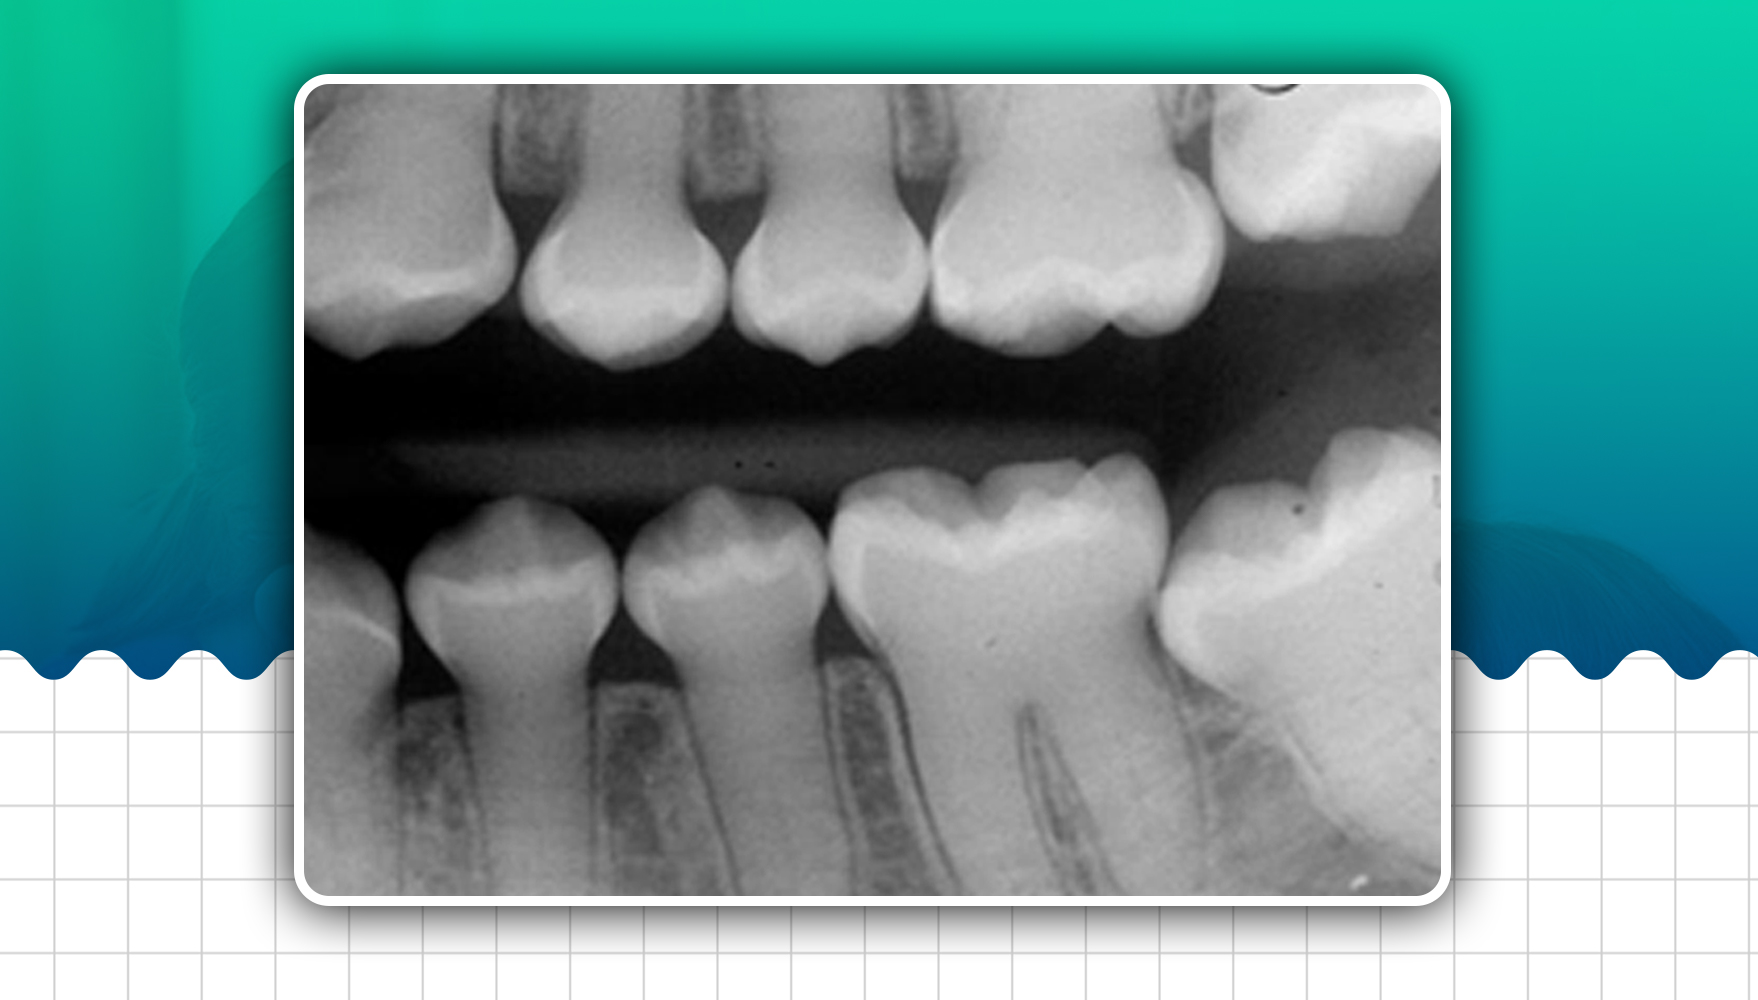

- Constriction of the cervical portion of the tooth that imparts a bullous appearance

- There may be slight to marked attrition of teeth, pulp, root and root canal: Partial or complete obliteration of pulp chamber. Pulp obliteration may take place before or after the eruption of teeth. Root canals may be absent or thread-like or may be blunted.

- Periapical radiolucency without pulpal involvement and periodontal ligament space widening

- Flame-shaped pulp canal: In some cases, the radicular portion of pulp cavities is very narrow, while the pulp chambers have a bulbous expansion terminating in a point deep to the occlusal aspect, which resembles 'flame.'

- Shell teeth: In Brandywine type, the tooth's enamel appears normal, while the dentin is extremely thin, and the pulp chambers are enormous. Teeth appear as 'shell teeth'. In addition, the tooth's roots are extremely short, so it seems as if enamel and dentin are surrounded by extremely large pulp chambers and root canals.